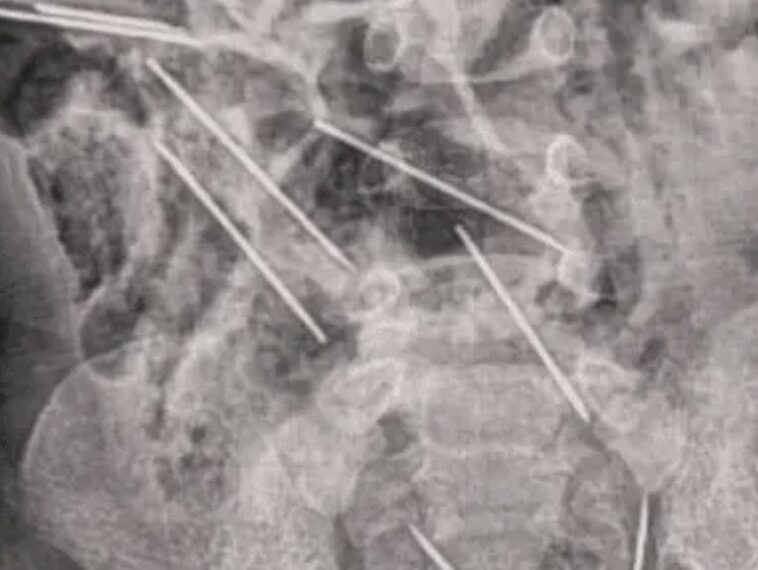

Al llegar al hospital la madre informó de lo sucedido a los médicos y éstos intervinieron rápido para ayudarlo, donde lo primero que hicieron fue sacarle una radiografía para determinar dónde estaban las agujas.

Luego de la radiografía los médicos notaron que algunas de estas agujas se encontraban muy cerca de los órganos vitales del bebé, por lo que tuvieron que someterlo a cirugía casi de forma inmediata debido al riesgo que estas representaban.

Pasaron cerca de dos horas desde que inició la intervención quirúrgica en el menor y los médicos lograron retirar las agujas del cuerpo del niño, y una alcanzó a hacer una lesión leve en el intestino delgado del menor.